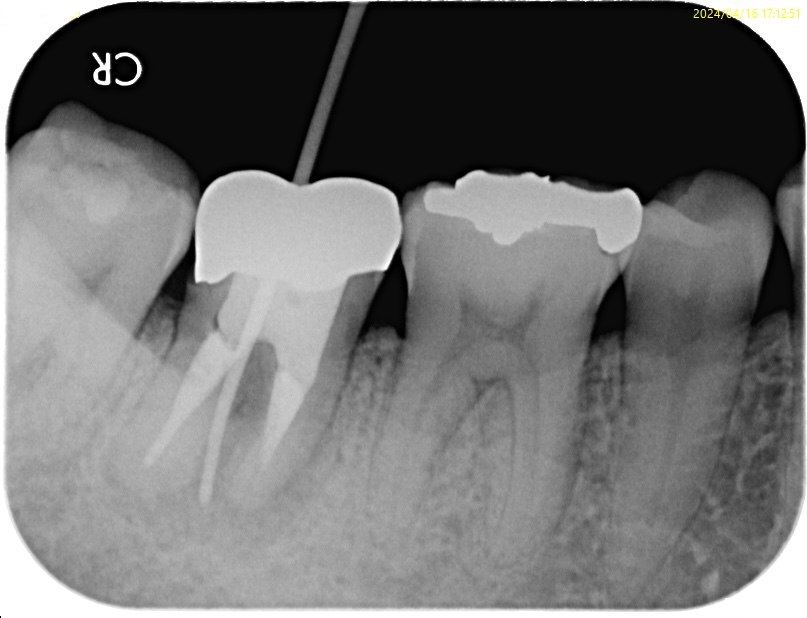

治療前

| 主訴 | 右下の奥歯が腫れてきたので診てほしい |

| 診断名 | previously treated Chronic apical abcess

今までに2回根管治療をしているということで、根管の上部3分の1が太く削られています。

根尖部も然り。

これ以上、通法の根管治療を行っても成功率は低いと判断。